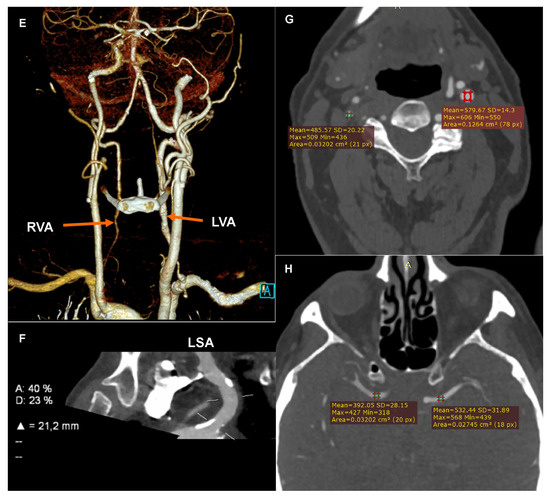

Computed tomography angiography (CTA): (A) Coronary CTA. Native phase. Axial reconstruction. Coronary artery calcium score measurement. The colors indicate the calcifications assigned to specific coronary arteries. (B) Coronary CTA. Angiographic phase. Curved multiplanar reconstruction (cMPR). Left circumflex (LCx). Measurement of the degree of stenosis. (C) Coronary CTA. Angiographic phase. Curved multiplanar reconstruction (cMPR). Left anterior descending (LAD). Measurement of the length of the myocardial muscle bridge. (D) Carotid CTA. Angiographic phase. Curved multiplanar reconstruction (cMPR). Brachiocephalic trunk (BCT). Measurement of the degree of ostial stenosis. The letter A indicates the level of vessel lumen measurement at the reference level, the letter B indicates the level of vessel lumen measurement at the level of maximum stenosis. Computed tomography angiography (CTA): (E) Carotid CTA. Angiographic phase. Volume rendering technique reconstruction (VRT). Arrows mark the recessive right vertebral artery (RVA) and the dominant left vertebral artery (LVA). (F) Carotid CTA. Angiographic phase. Curved multiplanar reconstruction (cMPR). Left subclavian artery (LSA). Measurement of the degree of stenosis. (G) Carotid CTA. Angiographic phase. Axial reconstruction. Measurement of the density of the proximal sections of the internal carotid arteries. Lower density of contrasted blood in the right carotid arteries. (H) Carotid CTA. Angiographic phase. Axial reconstruction. Measurement of the density of the cerebral arteries. Lower density of contrasted blood in the right cerebral arteries.

The CTA of the carotid and vertebral arteries performed using a 384-slice Siemens Force CT revealed a typical origin system of the aortic arch branch, numerous atherosclerotic plaques of various morphotic types in the aortic arch and its branches, significant ostial stenosis of the brachiocephalic trunk by 70–90% of the vessel lumen (Figure 1D), recessive right vertebral artery (Figure 1E), and ostial insignificant stenosis of the left subclavian artery (Figure 1F). In the CTA the right carotid arteries and the right cerebral arteries were characterized by a significantly lower lumen density compared to the contralateral side (Figure 1G,H), which may indicate impaired flow or its direction reversal. The CTA image of the carotid and vertebral arteries corresponded to significant stenosis of the brachiocephalic trunk with symptoms of the steal syndrome.